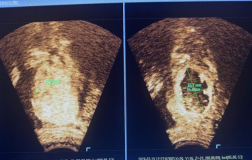

我院五疗康复科实施首例CT引导下三叉神经电极置入术

近日,我院五疗康复科与北京清华长庚医院疼痛医学科专家团队紧密协作,在影像科的支持配合下,开展首例CT引导扫描重建下三叉神经电极置入术。该技术的应用,为三叉神经痛等难治性神经病理性疼痛患者提供了精准、微创的治疗新选择,也标志着医院在该领域的诊疗水平实现新的突破。患者刘女...